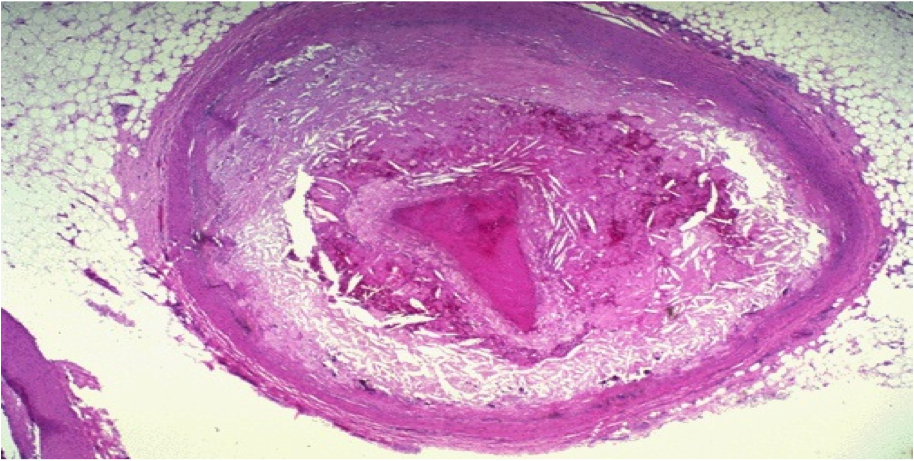

What is shown in this pic?

occlusive thrombus